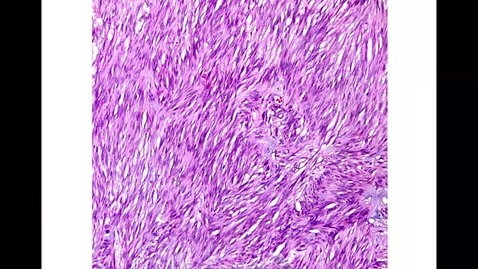

GYN Lab Endometrium, Myometrium, Germ Cell Tumors

Endometrium, Myometrium, Germ Cell Tumors M&R…